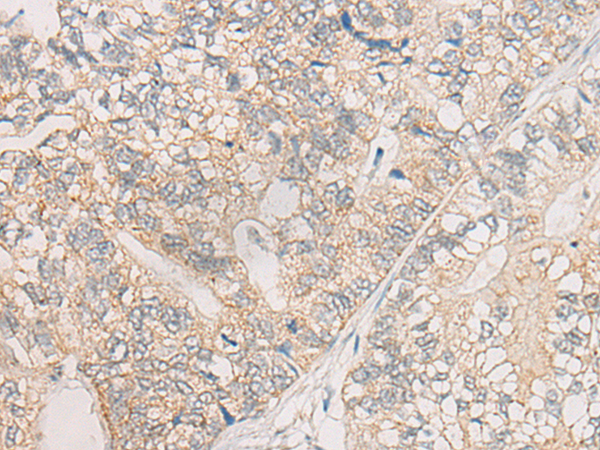

分类: 科研抗体货号: P00764别名: TRKB; trk-B; GP145-TrkB应用: IHC反应种属: Human, Mouse, Rat